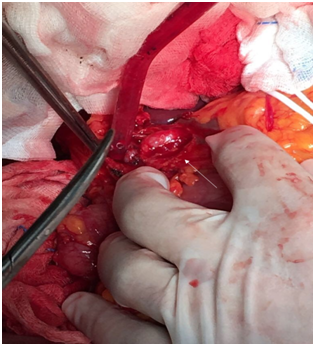

In multidisciplinary assessment, our hepato-bilio-pancreatic radiologist highlighted a periampullar resectable tumor and a celiac axis significant stenosis. Diagnostic angiography was then performed, which confirmed the celiac axis stenosis and revascularization was attempted, but proven to be technically infeasible. Surgical resection was decided. Intraoperative hepatic artery flow was severely compromised with GDA occlusion, confirming the celiac axis stenosis. A supra-celiac-aorto-hepatic bypass graft (uni-graft K-DV 8mm) followed by a cephalic duodenopancreatectomy with a dunking pancreato-jejunostomy, end-to-side hepatico-jejunostomy and piloro-jejunostomy was performed (Figures 3 & 4).

Figure 4Aortic-hepatic bypass graft.